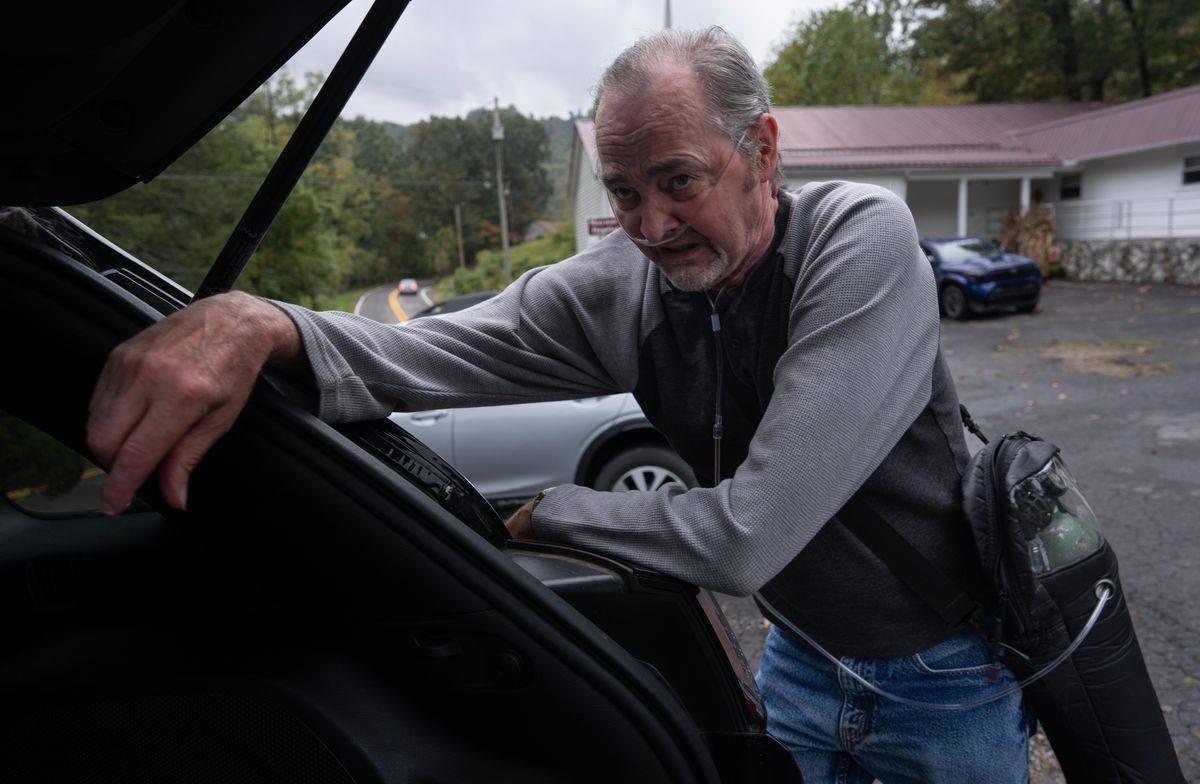

Experts say that’s because much of the easy-to-reach coal has already been extracted in West Virginia and neighboring Virginia and Kentucky, forcing miners to use massive equipment to eat through walls of quartz-filled sandstone to reach the remaining thin coal seams. This creates excess dust laced with shards of silica, which also cause lung cancer and kidney disease. It’s 20 times more toxic than coal dust, the major culprit of the past that often sickened older workers. The silica crystals embed in miners’ lungs, causing chronic inflammation and eventually irreversible scarring that peppers X-rays with chalky spots. It leaves proud, once-strong men skinny and weak. They choke on their food and gasp after just a few steps, cradling shiny cylinders that provide a lifeline of oxygen through tubes snaking into their nostrils.

“If you’ve ever about drowned — or anybody’s about drowned — they know what I’m talking about because I go through that every morning,” said Mark F. Powell, a fourth-generation miner from southern West Virginia who’s upset with Trump’s policies. “By the end of the day, I’m so tired. Sometimes I don’t even eat supper. I’ll come home and sometimes I’m not even able to take a shower. I’m not ashamed to tell it. I’ll lay on the floor and go to sleep.”

He said he wore his protective respirator throughout his nearly 30-year career, but was still diagnosed with a progressive form of complicated black lung and silicosis when he was 45. NIOSH certified his X-ray, allowing him to move to a job on the surface with no pay cut. Now, just four years later, he said he doesn’t have the wind to mow his lawn.

But sick miners say the cost, for them, is their lives. Even after removing all exposure to silica and coal dust, symptoms continue to worsen, typically resulting in only two options: A risky, expensive lung transplant or death.

“I feel like in our part of the country … we’re kinda forgotten about,” said John Robinson, a former miner from Nickelsville, Virginia, who uses a walking stick and oxygen after being diagnosed with the disease 12 years ago at age 47. “I don’t think it’s right.”

“They’re doing everything they can to hurt the working man,” he said, lugging his oxygen tank. “They ain’t worried about the miners or people in West Virginia or coal miners anywhere. All they’re worried about is the almighty dollar in D.C. They don’t care about the little people that put them there.”